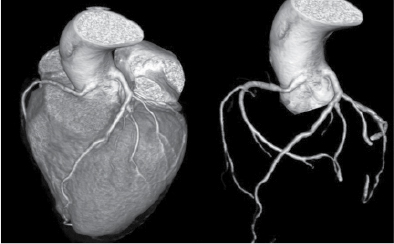

At Nizam’s Institute of Medical Sciences (NIMS), Hyderabad, 770 patients underwent CT-conventional coronary angiography (CAG), on 128-slice single source MDCT (SOMATOM Definition AS ± SEIMENS) during the last 3 years (unpublished data). On analysis, coronary artery anomalies were found in 23 patients (3%). Their ages ranged from 25 to 82 years. Majority of the cases were in 51 to 60 years age group. Among them, 17 were males. The most common anomaly seen was high take-off of coronary arteries, seen in 10 cases. Of them, 2 were having high origin of right coronary artery (RCA) (Fig. 1), 7 were having high origin of left main coronary artery (LMCA) and one was having high origin of both coronary arteries with acute kink at the origin of RCA. Anomalous origin of coronary artery from opposite sinus was seen in 8 cases (Figs. 2-5). RCA from left coronary sinus with interarterial course between aorta and right ventricular outflow tract was seen in 5 cases. Anomalous origin of left coronary artery (LCA) from right coronary sinus with interarterial course between aorta and right ventricular outflow tract was seen in 2 cases. Anomalous origin of left circumflex artery (LCx) from right coronary sinus with retroaortic course was seen in 1 case (Fig. 6). Separate ostia for left anterior descending artery (LAD) and LCx was noted in 3 patients (Figs. 7 and 8). Shepherd crook deformity of proximal segment of RCA was seen in 1 patient. Super-dominant RCA with absent LCx was seen in 1 patient (Fig. 9).

Figure 9. A patient aged 52/F having super-dominant RCA. LCx is absent.

Super-dominant RCA with absent LCx artery is an exceedingly rare congenital anomaly that can be confused with atherosclerotic total occlusion. There are a few such case reports in the literature.8 We observed one such case of super-dominant RCA with absent LCx. Single coronary artery is extremely rare with prevalence of 0.09% (5 out of 5,869 cases) in a study by Fujimoto et al.4 Its clinical implication is complex when the patient develops atherosclerosis in the proximal segment and it can be a challenging situation for either angioplasty or coronary artery bypass grafting (CABG).